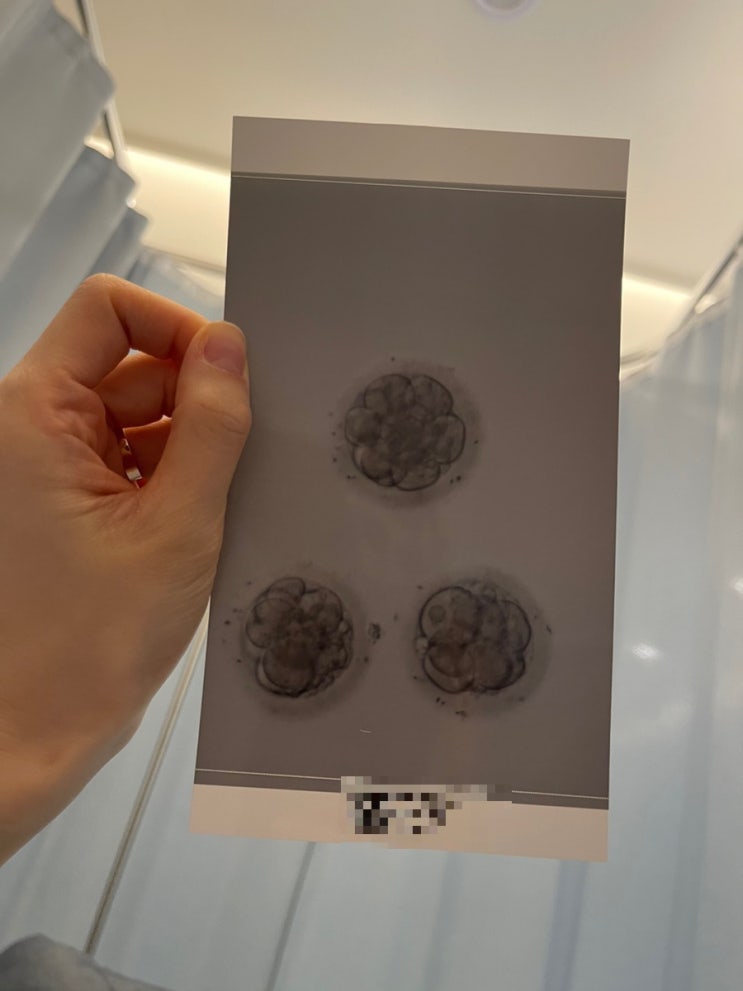

아기 심장소리도 듣고 했으니 카테고리를 임신일기로 변경해 보았다☺️ 내가 다녔던 난임병원 원장님께서...